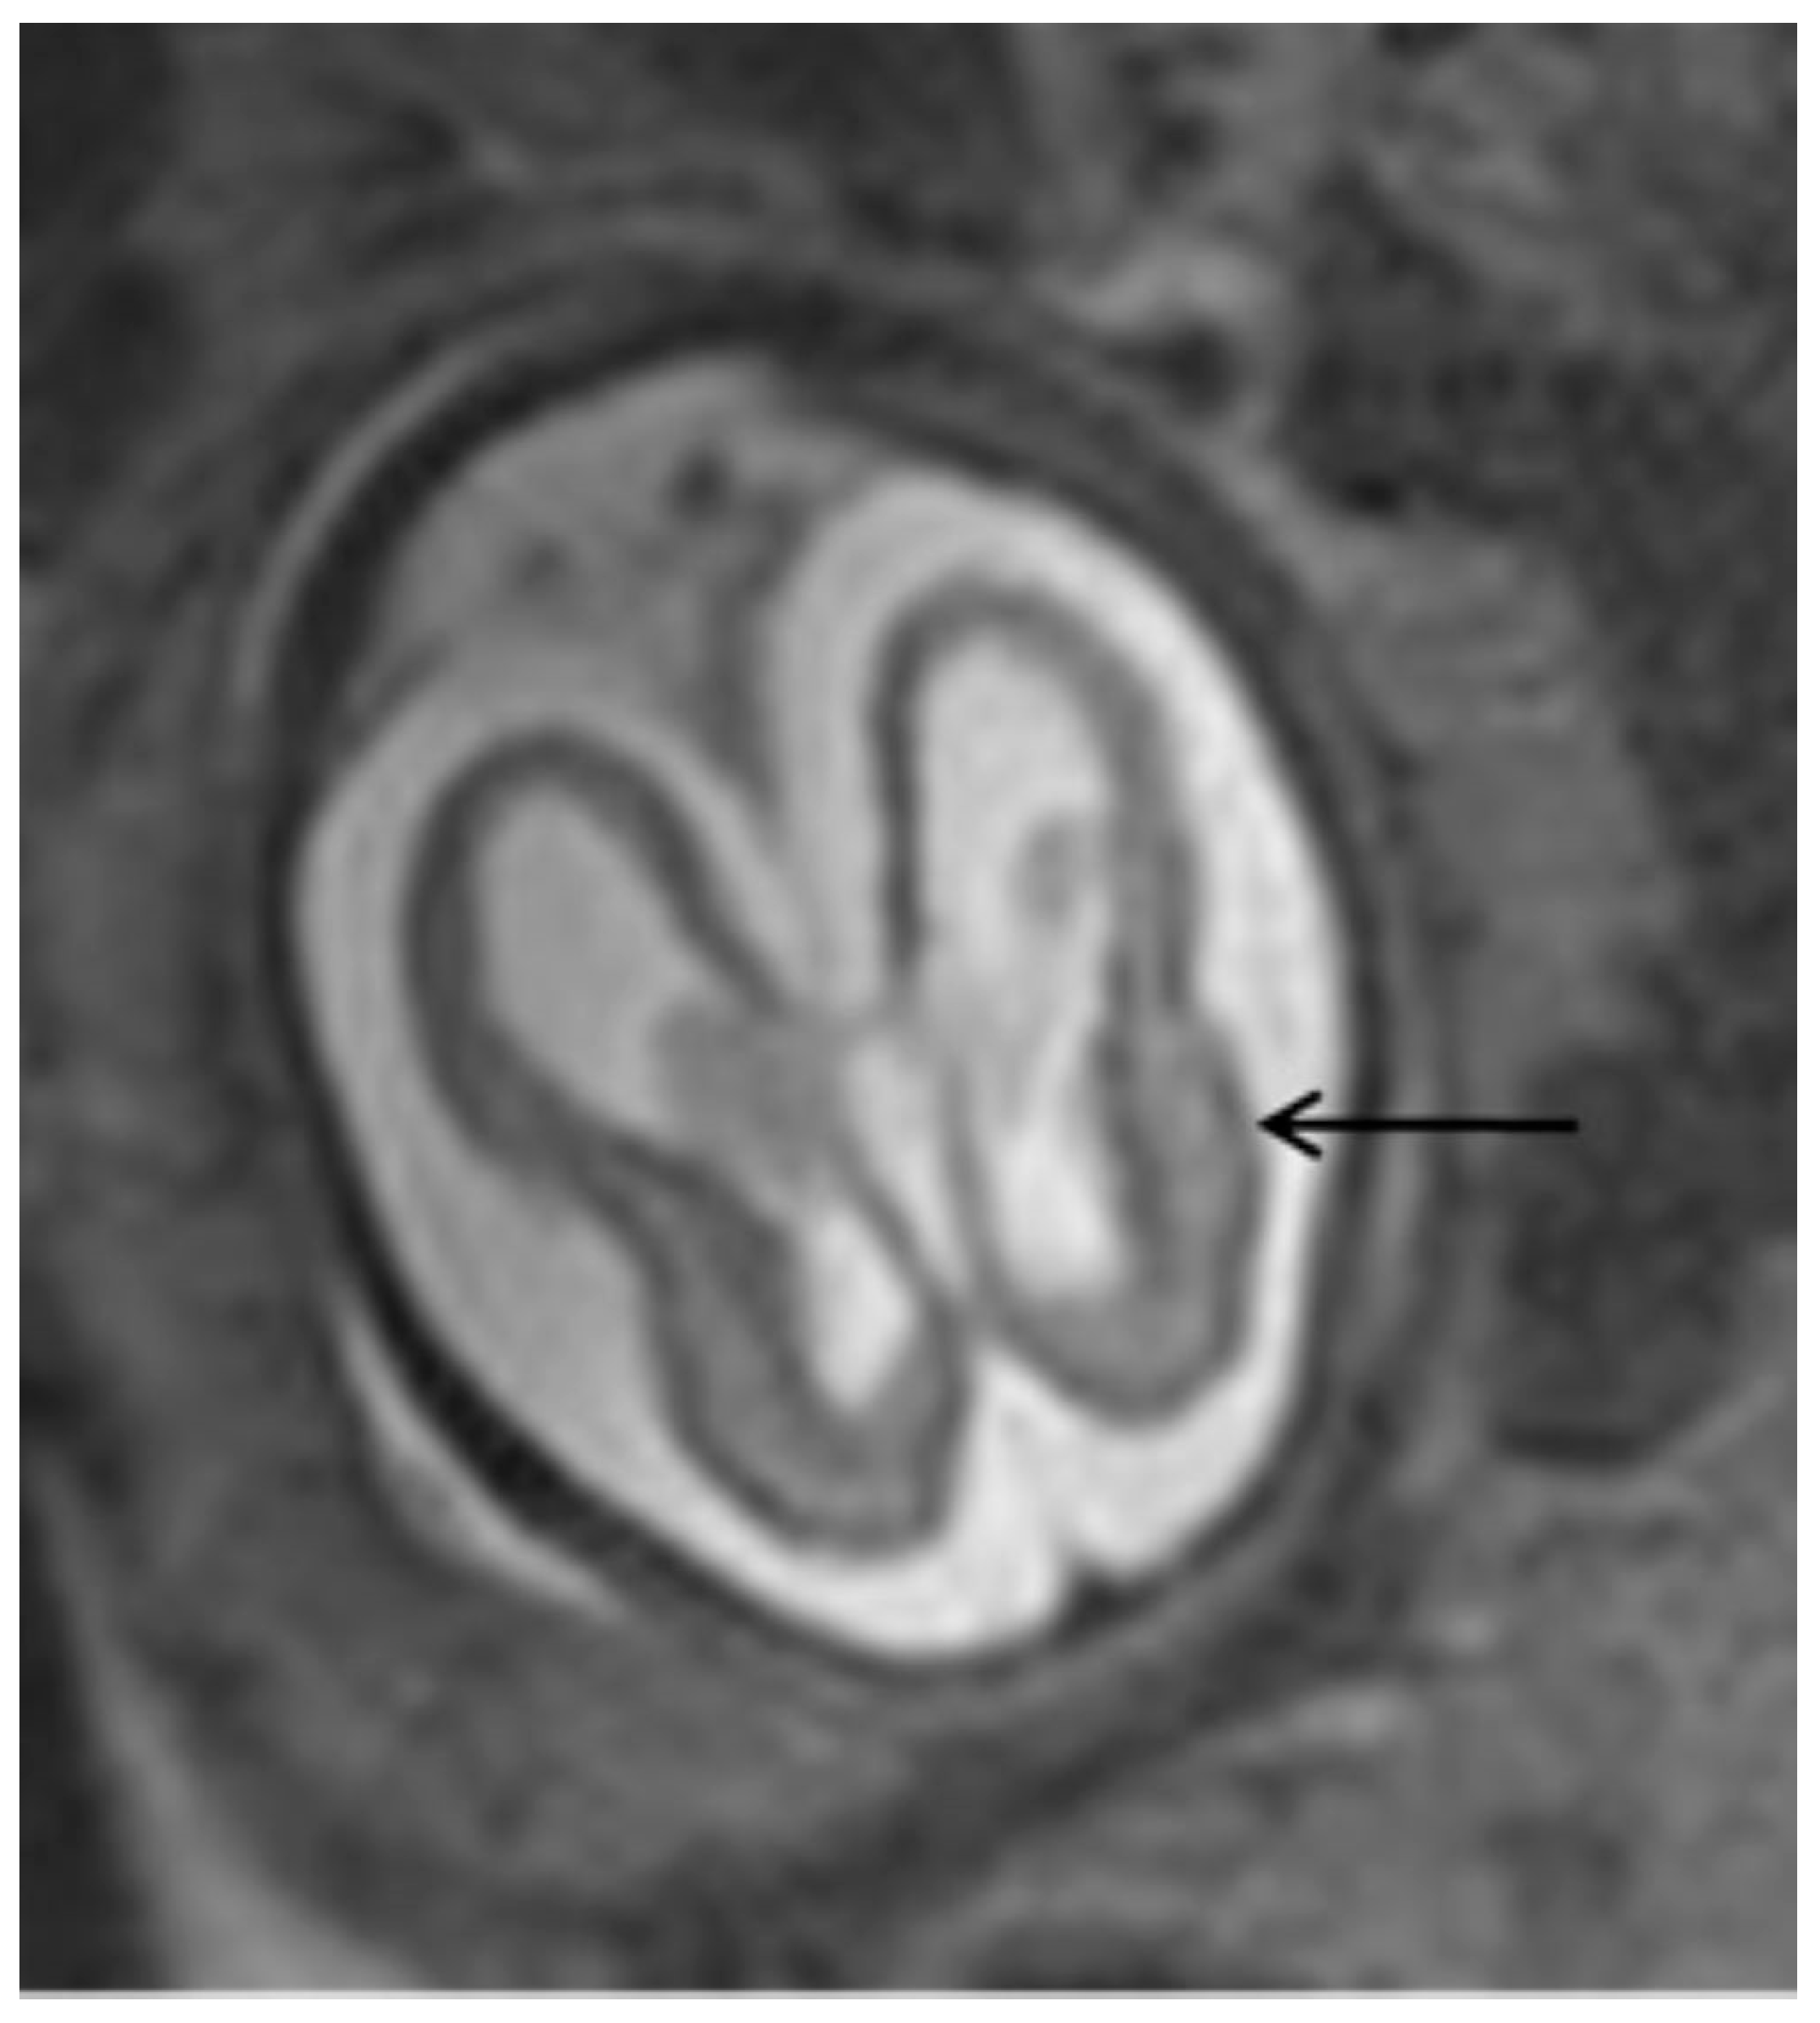

The most common ultrasonographic findings of intrauterine CMV infection are ventriculomegaly, periventricular changes, temporal cysts, and brain parenchymal lesions [25]. Magnetic resonance imaging (MRI) has been shown to complement ultrasonographic imaging in prenatal CMV assessment [25,26]. For example, Buca et al. [26] found that in 6% of ultrasounds in which no CNS abnormalities were seen, the MRIs were positive, but only in cases infected in the first trimester of pregnancy. The abnormalities seen on MRI are the same as those seen on ultrasound, but with a different incidence, with the most common abnormalities seen on MRI being temporal cysts and lesions in the brain parenchyma [25]. (Figure 3) It is known that the additional findings on MRI are due to the lack of studies using multiplanar neurosonography performed by an experienced professional, because when this is method is used, the results of both types of imaging are similar [26,27]. Intrauterine CMV infection is an indication for multiplanar (transvaginal) neurosonography [27]. The main changes seen on neurosonography are abnormal patterns of periventricular echogenicity (suggesting periventriculitis), ventriculomegaly, and echogenic focus in the brain parenchyma [27].

Figure 3.

T2-weighted MRI in axial view of fetal skull showing mild ventriculomegaly and cortical atrophy (arrow).

The absence of CNS ultrasound and MRI abnormalities during prenatal care is an important prognostic factor, as a very small percentage of newborns are symptomatic (1.5%) or have abnormal neurodevelopment (3.1%) or hearing loss (up to 11.4%) [26]. These abnormalities are associated with seroconversion in the first trimester of pregnancy, except for hearing impairment, which also occurred with seroconversion in the second trimester in 7% and in the third trimester in 0% [26]. CNS abnormalities seen on ultrasound and MRI are not specific to CMV infection, but are indicative of intrauterine infection [26,27]. The virus reaches the brain via the hematogenous route, entering the cerebrospinal fluid and causing inflammation of the choroid plexus and meninges [27]. This is the reason why the ventricular and periventricular lesions appear before the brain parenchyma lesions [27]. Figure 4 shows the categorization of intrauterine CMV infection according to Khalil et al. [31].